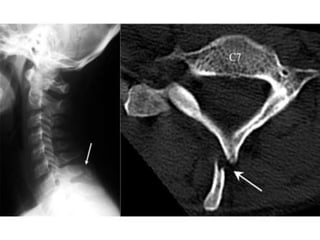

Clay Shoveler’s Fracture

Oblique avulsion fracture of a spinous process C6-T1

 C7>C6>T1

Best seen on lateral view

Powerful Hyperflexion injury(shoveling)

Stable fracture

Common in

motor vehicle accidents

sudden muscle contraction

direct blows to the spine

Ap view show ghost sign with 2 spinous processes ???